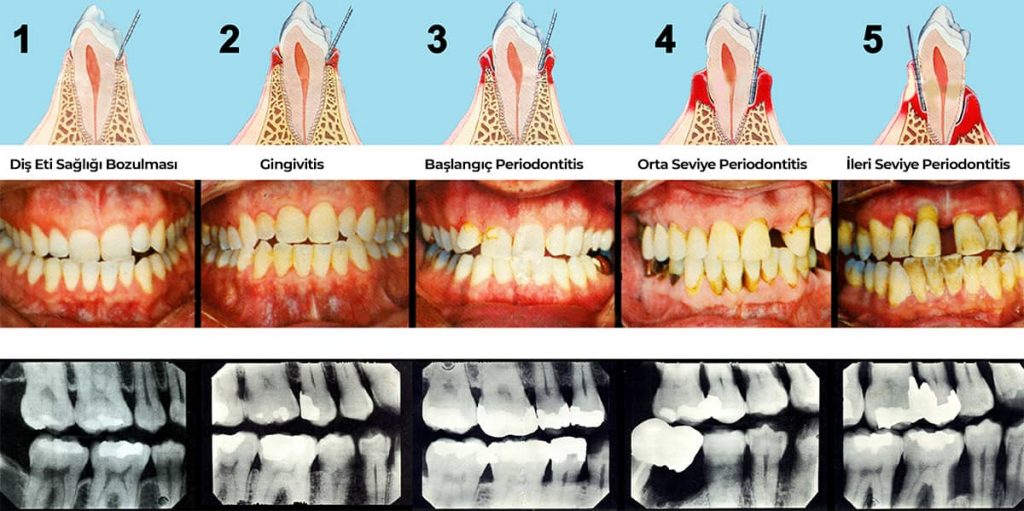

Periodontal hastalıklar, diş ve diş eti dokularını olumsuz etkileyen diş eti hastalığı olarak bilinir. Periodontal hastalıklar iltihabi hastalıklardır. Yetişkin insanlarda diş eti hastalıkları daha yaygın görülür ve diş kayıplarının çoğu diş eti hastalıkları yüzünden gerçekleşir. Ancak bu hastalıklar erken teşhis ile kolay ve başarılı bir şekilde tedavi edilebilmektedir.

Diş eti hastalıkları, diş eti iltihabı (gingivitis) ile başlar. Aslında gingivitis diş eti hastalığının erken dönemidir denilebilir. Gingivitis döneminde diş etleri, kanamalı, kırmızı ve hacimce genişlemiş yapıdadır. Diş eti hastalıkları erken dönemlerinde kişiye çok fazla rahatsızlık vermeyebilir. Tedavi edilmediği sürece sıradan bir diş eti hastalığı olan gingivitis periodontitise ilerleyerek diş eti ve dişleri destekleyen kemik yapıda da geriye dönüşü olmayan hasarlar bırakabilir.

Periodontitis, diş eti hastalıkları arasında en ilerlemiş olanıdır. Dişleri destekleyen diş eti dokusunun yanında alveol kemiğinde de hasara yol açar. Diş ve diş eti arasında "periodontal cep" denilen bir cep oluşur ve bu cebin içinde diş taşı ve plak gibi birçok ağız hijyenini bozabilecek şey oluşur. Bu bakteriyel oluşumların diş taşı temizliği ile temizlenmesi gerekir. Ceplerin temizlenmediği durumlardaysa enfeksiyonun yerleşmesi ve hastalığının daha fazla ilerlemesini kolaylaştırıcı bir rol alır. Bu hastalık ilerledikçe dişler sallanmaya hatta düşmeye başlayabilir.